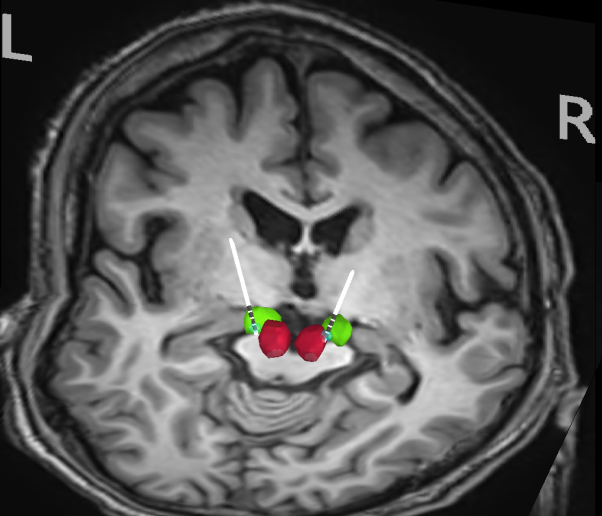

手术靶点位置

考虑到张先生病程较长、药物控制不佳、功能受损严重等情况,功能疾病组团队决定通过新靶点丘脑底核后部区域,为他进行脑深部电刺激术。手术当日,阿布都克尤木·吉力力团队在高清核磁影像融合技术的引导下,向靶点位置精准植入刺激电极,术中临时放电刺激即见老人手部震颤显著改善。